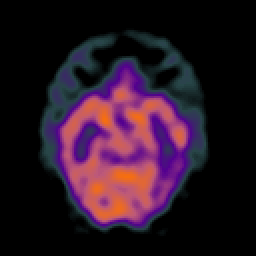

SPECT TC Study #1 -- Slice #21

[Home][Help][Clinical][Tour 1][Tour 2][Tour 3] Slice 21